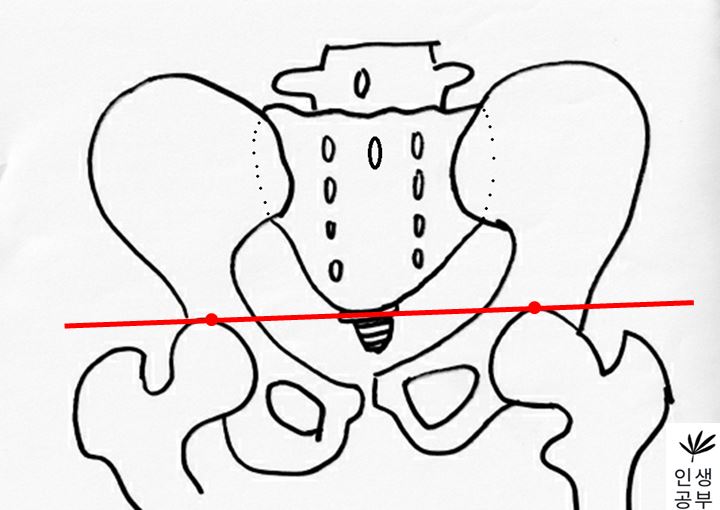

2) 대퇴골두(Femoral head) 최상단에 양쪽에 각각 한개씩 점을 찍어줍니다.

3) 두 점을 연결하는 선을 긋습니다. 이 선의 이름은 대퇴골두선(FHL : Femur Head Line)이라고 합니다.